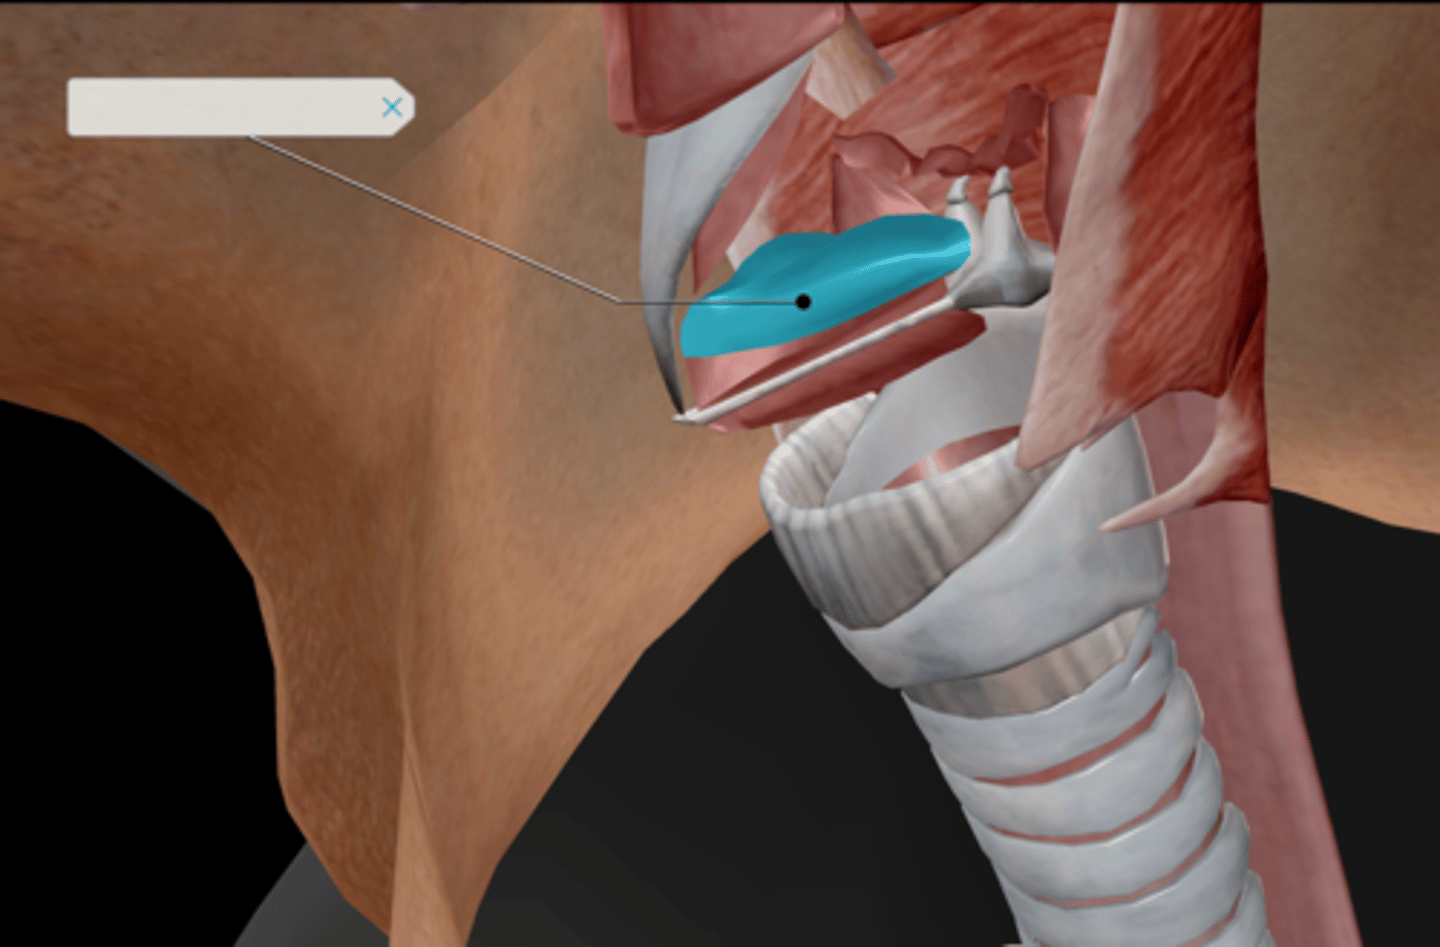

Larynx

Epiglottis

Thyroid cartilage

Cricoid cartilage

Vocal ligament

Vocal folds

Vestibular folds

Trachea

Tracheal cartilaginous rings